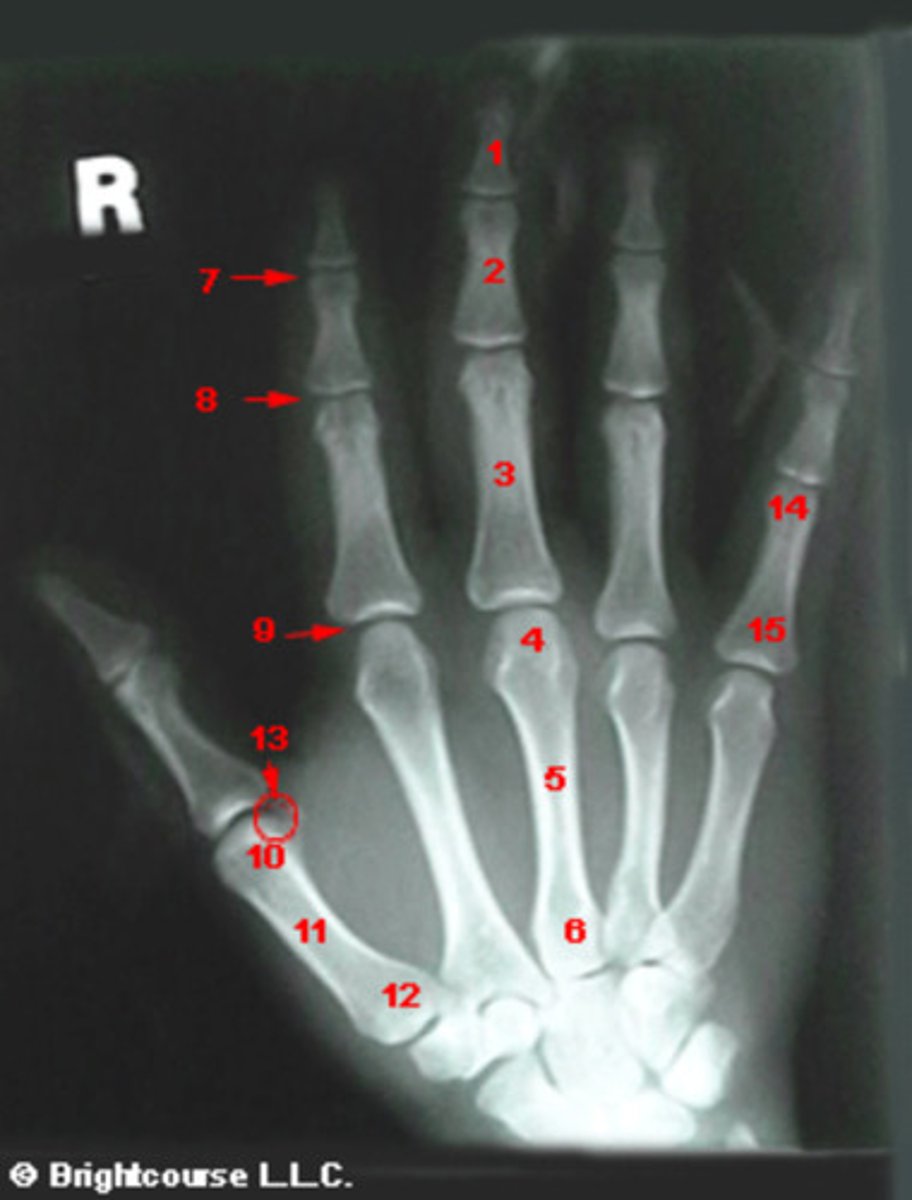

PA Hand

What is name of the radiographic projection?

Capitate

What structure is indicated by number 7?

Scaphoid

What structure is indicated by number 1?

What structure is indicated by number 2?

What structure is indicated by number 3?

Transverse fracture of the distal radius

What structure is indicated by number 4?

Positive ulnar variance

What structure is indicated by number 5?

Lunate

Trapezoid

What structure is indicated by number 6?

Hamate

What structure is indicated by number 8?

Styloid process of ulna

What structure is indicated by number 13?

Styloid process of radius

What structure is indicated by number 12?

Triquetrum

Hook of the hamate

What structure is indicated by number 9?

Trapezium

Base of the first metatarsal

What structure is indicated by number 10?

Metacarpophalangeal joint

Base of the 3rd metacarpal

Shaft of 3rd metacarpal

Distal interphalangeal joint